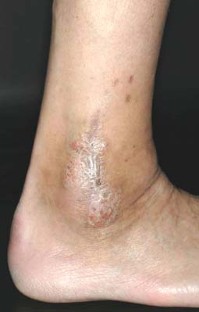

Abb. 1